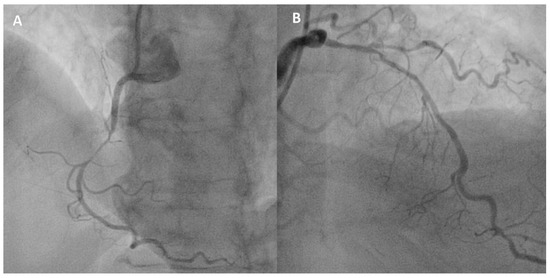

2. Case Vignette